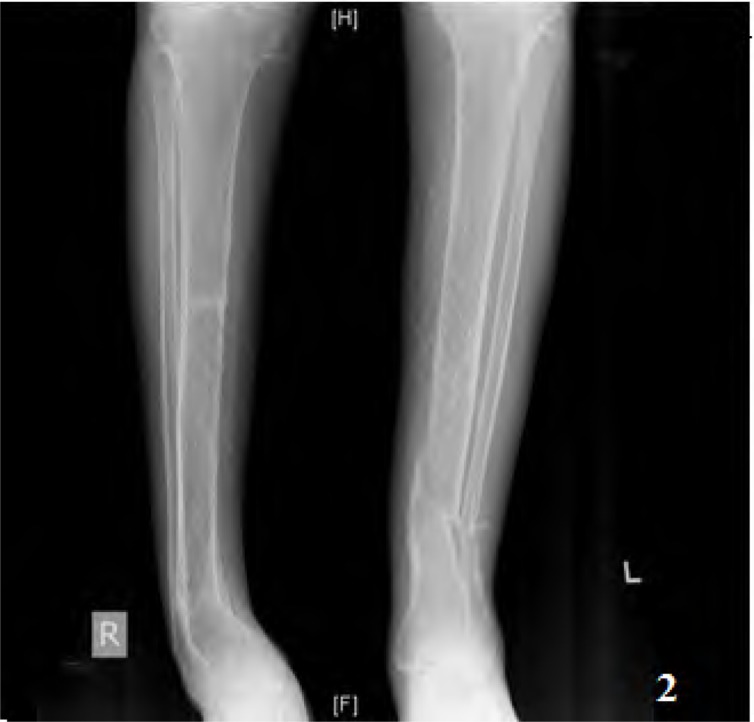

Results: Of the 380 patients with clinically suspected pSS, 25 had RTA. The median age was 32 (18-60) years. Nineteen patients had complete RTA. Six had incomplete RTA. Only 10 patients (40%) had symptoms related to RTA at presentation. Sixteen patients (64%) had present or past history of hypokalemic paralysis. Pseudofractures were seen in 7 patients and an additional 2 had subclinical radiological osteomalacia. Majority of the patients (61.2%) had a normal 25(OH) D3 level. Those with osteomalacia had significantly lower serum phosphate, blood ph and higher alkaline phosphatase. Serum calcium and 25(OH) D3 levels were not significantly different between patients with osteomalacia and those without.